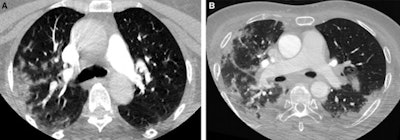

Axial CT images from head and neck CT angiography demonstrate (A) predominantly unilateral peripheral patchy ground-glass opacities, highly suspicious for COVID-19 pneumonia and (B) bilateral and multifocal, predominantly peripheral ground-glass opacities, with subpleural consolidations abutting the visceral pleura, with additional linear opacities, very highly suspicious for COVID-19 pneumonia. Images courtesy of Stroke.They found 20 (67%) patients in the COVID-19-positive group and two (7%) in the COVID-19-negative group with lung findings highly or very highly suspicious for COVID-19 pneumonia.